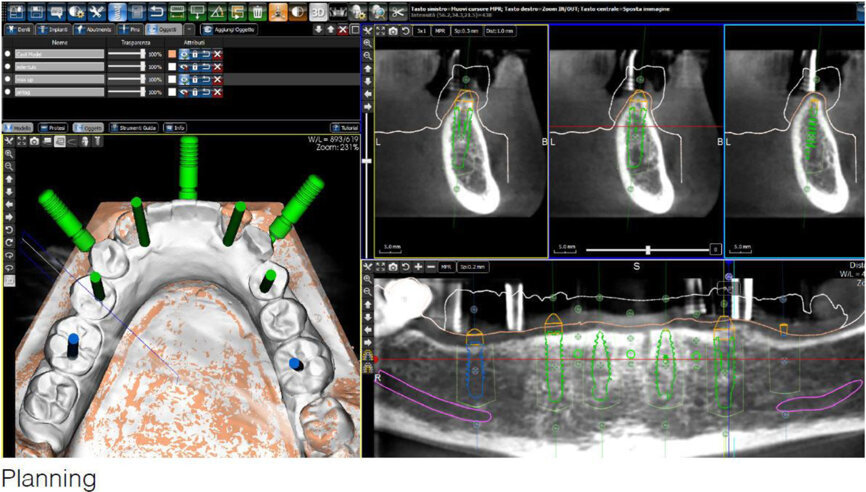

Fig. 4: Screenshot of the virtual implant planning for positions #36, 35, 33, 42 and 46, showing occlusal, sectional and panoramic views.

After extraction of the painful and extremely mobile teeth #41, 31 and 32 and adaptation of the existing RPD, a cone beam computed tomography scan (PaX-Uni3D, VATECH) with a 5 x 8 cm field of view, 85 kVp generator voltage, 5.5 mA generator current and 0.2 mm voxel size was performed to proceed with the detailed implant planning (Fig. 4). Based on the anatomical conditions and prosthetic planning (i.e. tooth set-up for the provisional RPD), six implants were virtually planned (3Diagnosys, 3DIEMME) in positions #46, 44, 42, 33, 35 and 36. As the implant positions #42 and 33 interfered with teeth #43 and 33, a two-step procedure with two surgical templates was planned for the guided implant placement (Figs. 5a & b). The templates were fabricated stereolithographically (DS3000 and XFAB, DWS) according to the virtual implant planning. Based on the same digital file (Figs. 6a–c), a provisional fixed dental prosthesis (FDP) was prepared preoperatively, allowing for an intra-oral adaptation between the abutments and the framework in order to achieve a passive fit (Figs. 7a–d).